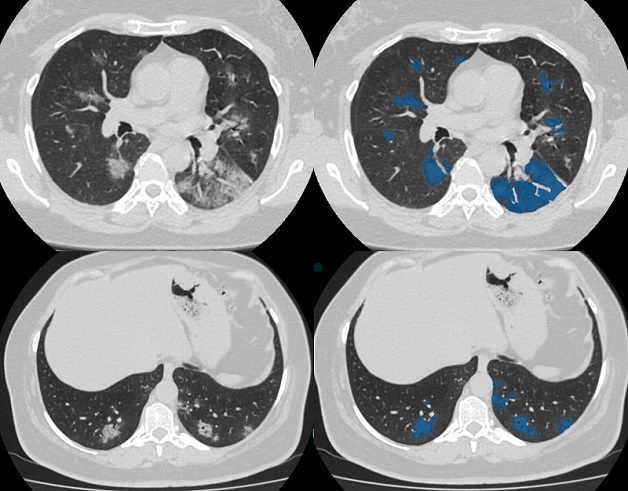

4. Một số hình ảnh chụp CT não tại TCI

Hệ thống Y tế Thu Cúc TCI hiện đang ứng dụng kỹ thuật chụp cắt lớp vi tính đa dãy vào trong thăm khám và chữa trị bệnh. Tùy vào mục đích chỉ định và nhu cầu của khách hàng, bác sĩ sẽ đưa ra phương án tối ưu nhất cho khách hàng, đảm bảo an toàn và thu được kết quả chính xác. Dưới đây là những hình ảnh ghi lại quy trình chụp CT não tại Thu Cúc TCI. Nếu bạn cần tìm hiểu thêm về phương pháp này, đừng ngại ngần liên hệ với chúng tôi để được giải đáp chi tiết về quy trình, chi phí chụp CT não!